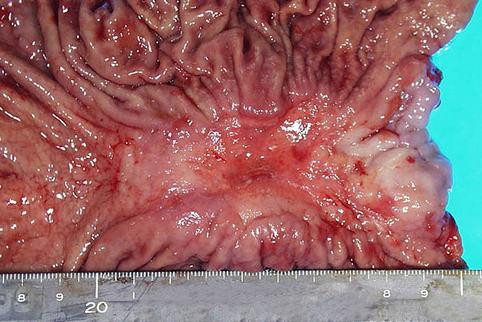

疾患(病理主体)の分類悪性上皮性腫瘍/腺癌

部位(臓器別)胃(部位)/体部

検査方法マクロ

腫瘍の肉眼分類3型(潰瘍浸潤型)/

病変の最大径(ミリ)40以上

腫瘍の深達度s(a)